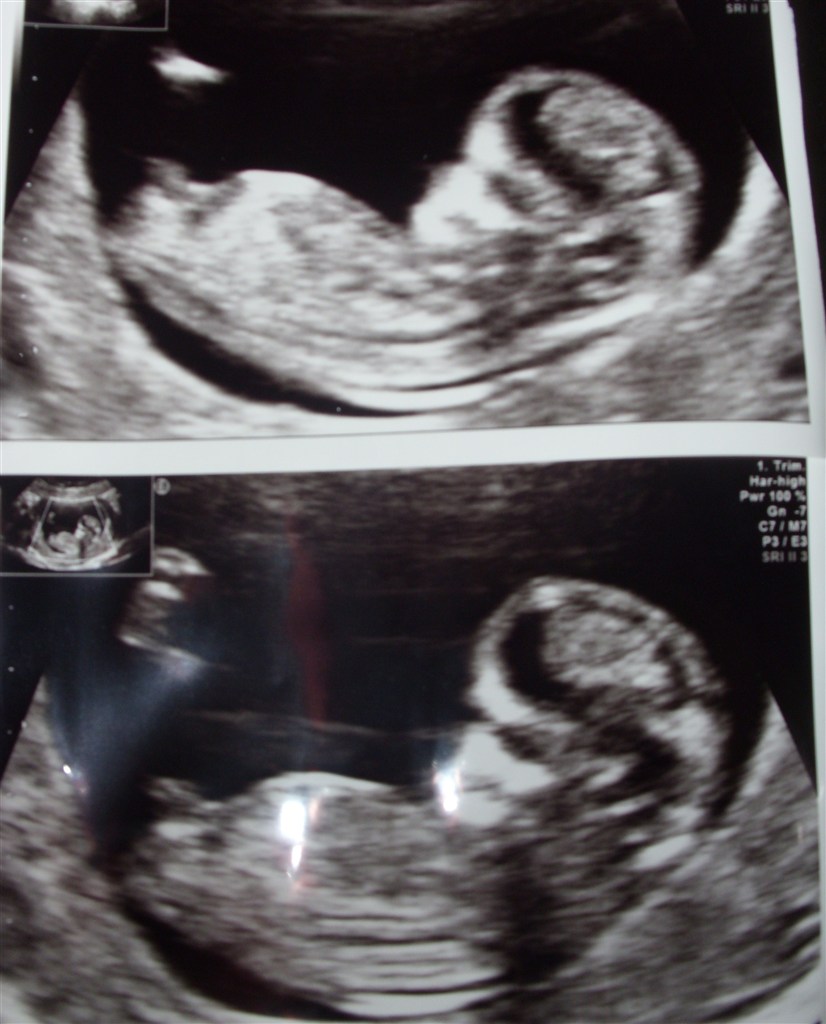

Har været til NF i morges og det var så stort

Vi skal have en lille vildbasse.

Den hoppede og dansede og ville ikke ligge stille.

Blev sat til den 27 september på min onkels fødselsdag